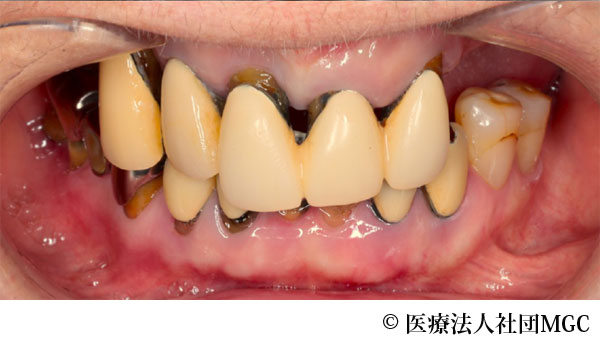

【症例5】上下All-on-4(オールオンフォー)

- 治療前

- 治療後

- 治療名

- 上下All-on-4(オールオンフォー)

- 費用

- 7,208,300円(税込)

- 期間

- 6ヵ月

歯を全体的にきれいに治してほしいとご来院されました。

ご相談の結果、患者様の生活の質(QOL)を向上させ、しっかり噛め、審美的にも重視した、上下All-on-4(オールオンフォー)を行いました。

機能性、審美性ともに改善し、満足していただけました。